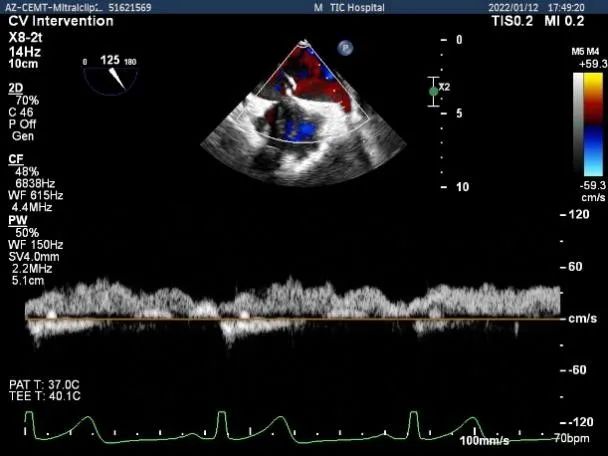

二尖瓣返流频谱呈全收缩期

肺静脉血流频谱呈收缩期反向

肺静脉血流频谱逐渐恢复正向

肺静脉血流频谱完全恢复正向